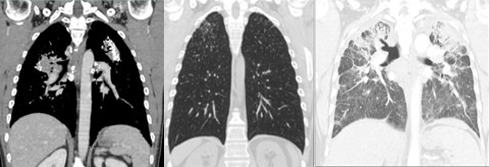

Sadly, both songs highlight that there are no doctors or medicines that can cure their ailments, for silicosis is an irreversible disease caused by silica dust and other minerals which, once inhaled, settle in the pulmonary alveoli, causing a chronic inflammatory reaction.

Over time, healthy tissue is replaced by fibrous scarring: the lungs become stiff, lose elasticity, and the surface area available for the exchange of oxygen is reduced. This is why respiratory capacity progressively decreases, leaving miners short of breath even during the simplest of tasks.

Although silicosis does not cause dysphonia directly, the ensuing respiratory disorders can affect the voice: chronic coughing irritates the throat and vocal cords, while breathing difficulties hinder breath control, causing hoarseness and a lower tone.